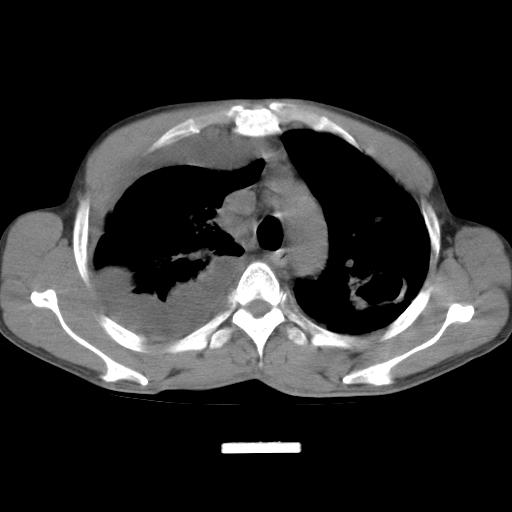

男性,44岁,结核病史多年。现胸闷气短,咳嗽,偶咳血。

右侧胸腔积液

右肺下叶不张

1、右侧大量胸腔积液伴右肺压缩性膨胀不全,建议抽液治疗后复查 2、两肺继发性tb伴空洞形成。

1)两肺继发性肺结核伴空洞形成,左肺多发性结核球。2)右侧大量胸腔积液伴右肺部分膨胀不全。3)纵隔淋巴结肿大。

1,双肺多发结节 并空洞影改变, 左侧胸腔积液并部分包裹, 结合原病史首先考虑结核. 但也不除外其它.

吉大一院胸水抽检结果:结核性胸水